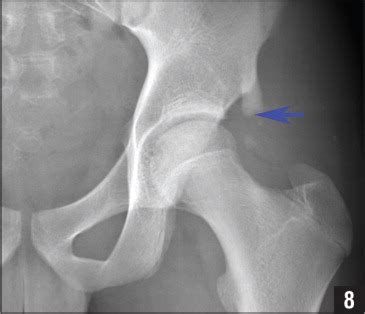

Avulsion fracture of the anterior superior iliac spine ...

Avulsion fracture of the anterior superior iliac spine ... from bjsm.bmj.com